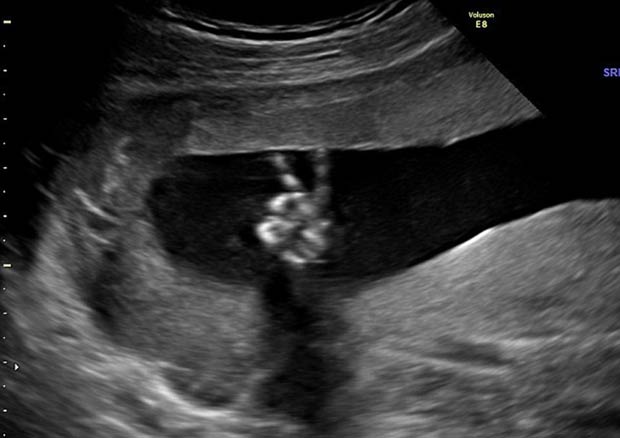

İngiliz anne adayı Dee Parsons'un 20 haftalık hamileyken çekilen ultrason görüntüsü ülkede ilgi odağı oldu.

İngiliz medyasına konuşan 35 yaşındaki Dee Parsons ve eşi bebeklerinin hareketinin 2'nci Dünya Savaşı boyunca sürekli zafer işaretiyle halkın karşısına çıkan eski Başbakan Winston Churchill'i çağrıştırdığını ve bu yüzden erkek olması durumunda çocuklarına Winston adını vereceklerini belirtti.Daha önce bir kız çocuğu dünyaya getiren Parsons, kızının da ultrasonda baş parmağını havaya kaldırarak poz verdiğini iddia etti.

Bebeklerinin barış ile özdeşleşen bir hareket yapmasından dolayı kendilerini iyi hissettiklerinin altını çizen çift, İngiliz Daily Mail gazetesine verdikleri mülakatta "Uzun bir zamandır kötü bir dünyaya bebek getireceğimizi düşünüyor ve endişeleniyorduk. Bu görüntü içimizi rahatlattı" ifadelerini kullandı.